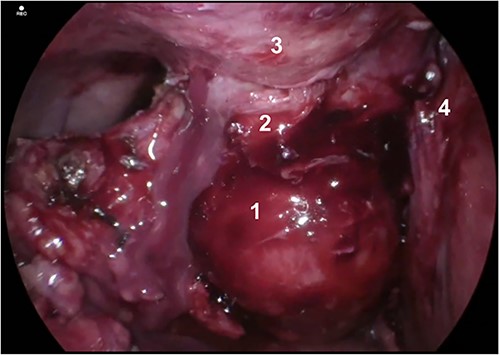

Post-drain removal, the patient was booked for elective laparoscopic cholecystectomy. An infraumbilical port was inserted to achieve pneumoperitoneum, and further ports were inserted based on ergonomics (Fig. 3). Initial adhesiolysis and dissection of the gallbladder from the greater omentum and anterior abdominal wall proved challenging. After freeing the fundus, the gallbladder was found to be full of pigmented stones, many of which had migrated into the fistula tract (Fig. 4). The fistula tract was opened from the intra-abdominal aspect and all gallstones were laparoscopically retrieved, with some stones found to have migrated as far as the umbilical port in the midline (Fig. 5). A subtotal cholecystectomy was performed, leaving a small part of the Hartmann’s pouch in situ as it was unsafe to dissect lower. The pouch was closed with absorbable sutures. Drains were placed in the subhepatic space and pelvis.

Gallbladder and fistula communicating with abdominal wall. Structures depicted: 1. Gallbladder, 2. Fistula, 3. Abdominal Wall, 4. Liver.